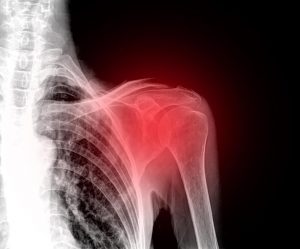

على الرغم من أن ألم الكتف هو حالة مزعجة للغاية تجعل من المستحيل القيام بالأنشطة اليومية الطبيعية، يمكنك تخفيف ألم الكتف بصورة طبيعية بدون الحاجة للجوء للأدوية.

ألم الكتف هو حالة غير مريحة تسبب الشعور بالإعاقة لأن مفصل الكتف هو ما يمسح لك بالتفاعل بكفاءة مع محيطك.

يوجد عدة أنواع من الإصابات التي قد تسبب الألم، التورم وعدم القدرة على الحركة. وقد تصاب بالتورم المزمن إذا لم تحصل على أي اهتمام طبي.